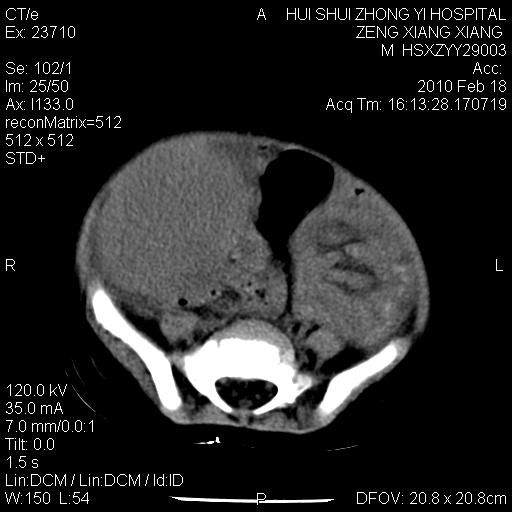

标题: PED3106:男,2岁,腹胀1月。 [打印本页]

标题: PED3106:男,2岁,腹胀1月。

定位腹膜后,肾上腺来源;

定性:恶性神经源性,肾上腺神经节母细胞瘤可能性大。

鉴别:肝母、肾母、肝脏中胚层错构瘤。

依据:年龄、有钙化,肾脏及肝脏受压移位。

肝母细胞瘤可能性大,右肾形态大体可见,不支持肾母细胞瘤,右肾移位不明显,肾上腺神经母细胞瘤可能性不大。